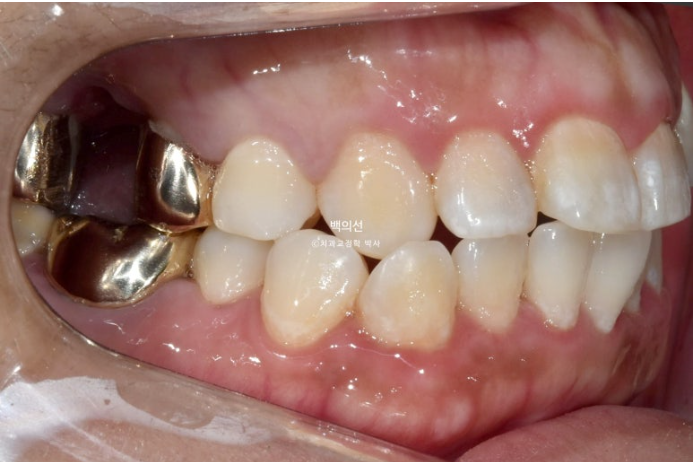

턱의 비대칭도 있어 앞니 치아중심선이 약 2mm 어긋나 있으며 아래턱이 돌아간 우측으로 송곳니와 어금니가 반대 교합입니다.

덧니도 있고 돌출도 심하니 작은어금니 4개 발치교정이 필요한 상황입니다.

그런데 파란 화살표 부분에 큰어금니가 하나 없습니다.

오래 전 큰어금니가 빠진 부분을 브릿지로 치료해 놓은 상태입니다.

치료의 편의성을 위해서는 작은어금니 4개 발치가 필요하나 브릿지 자체가 오래되기도 해서 파란 화살표쪽 분악은 추가적인 소구치 발치 없이 브릿지를 잘라내어 큰어금니 빈공간에 이용하기로 합니다.

그러면 작은어금니 발치갯수를 4개에서 3개로 줄일 수 뿐더라 오래전 큰어금니 빠진 자리를 임플란트 없이 교정으로 메꿀 수 있는 장점이 큽니다.